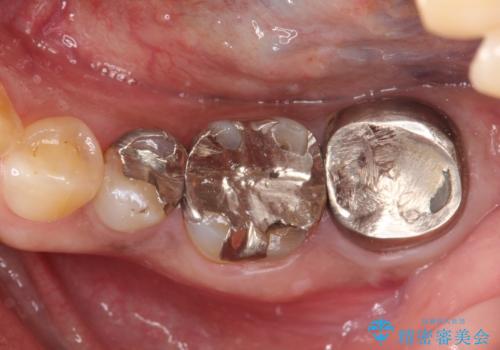

以前治療した歯が痛む 銀歯をセラミックに